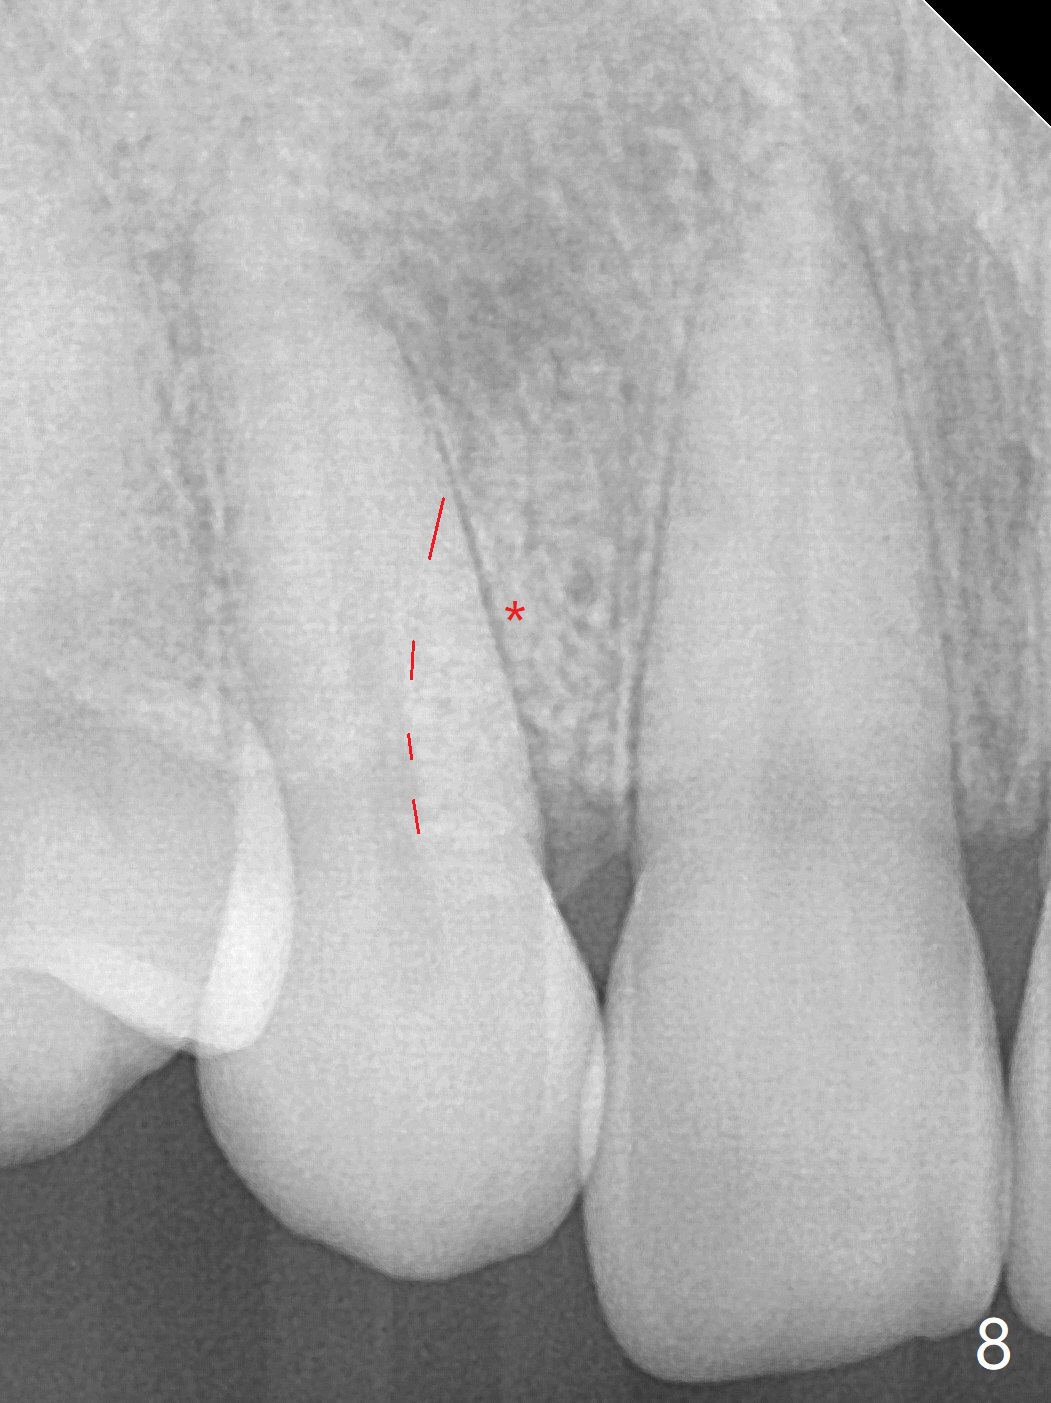

A 54-year-old woman seeks treatment for the tender upper right lateral incisor (Fig.1-4: 2 because of palatal cervical caries (Fig.3 <) and periapical radiolucency (*)), which overlaps with the palatal canine (3). One of treatment options is to extract the lateral and to orthodontically move the canine to the position of the lateral, particularly the root (Fig.5 arrow). When the lateral is removed, the labial bone of the canine is thin (Fig.6). Allograft is placed (Fig.8 * and dashed line), covered with Amnion-Chorion Allograft (Bioxclude) and sutured with 4-0 PGA (Fig.7). The wound heals 9 days postop (Fig.9,10). The patient is grateful because of no pain, which she thinks is due to bone graft, whereas Amnion-Chorion membrane is another contributory factor. The lateral root convexity remains 1 month postop (Fig.11 *); she is undecided upon orthodontic treatment.